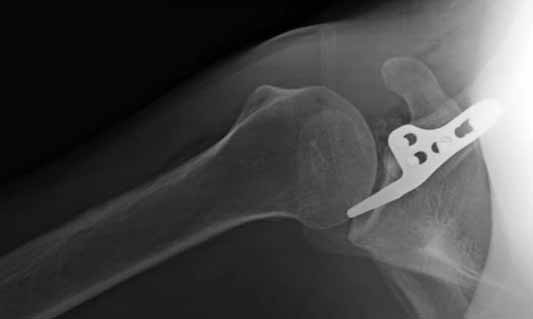

Re: ключичная пластинка

Отправитель: Серж 24 Июнь 2011, 13:42

foto 3

3.JPG